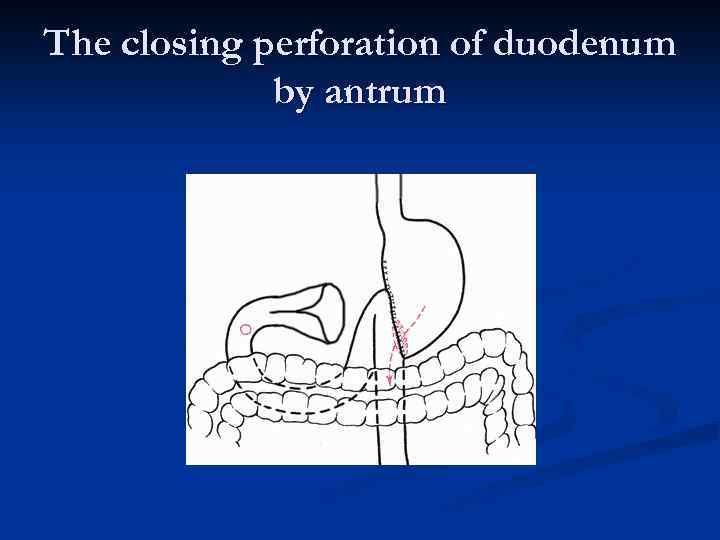

The closing perforation of duodenum by antrum

The closing perforation of duodenum by antrum